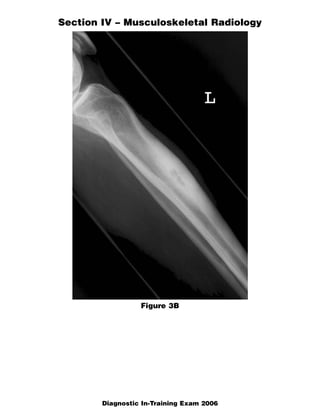

This document contains a radiology case study with 4 images (Figures 1-4) and accompanying questions. Figure 1 shows a lateral cervical spine x-ray. The diagnosis is ankylosing spondylitis based on diffuse bony ankylosis throughout the cervical spine. Figure 2 shows MRI images of the knee with a diagnosis of discoid meniscus due to excessive meniscal tissue. Figure 3 shows x-rays of the leg with a diagnosis of Brodie's abscess, seen as an elongated lytic lesion in the tibia. Figure 4 shows knee images of a 13-year-old boy with a diagnosis of chondroblastoma, seen as a well-defined lesion in the proximal tib